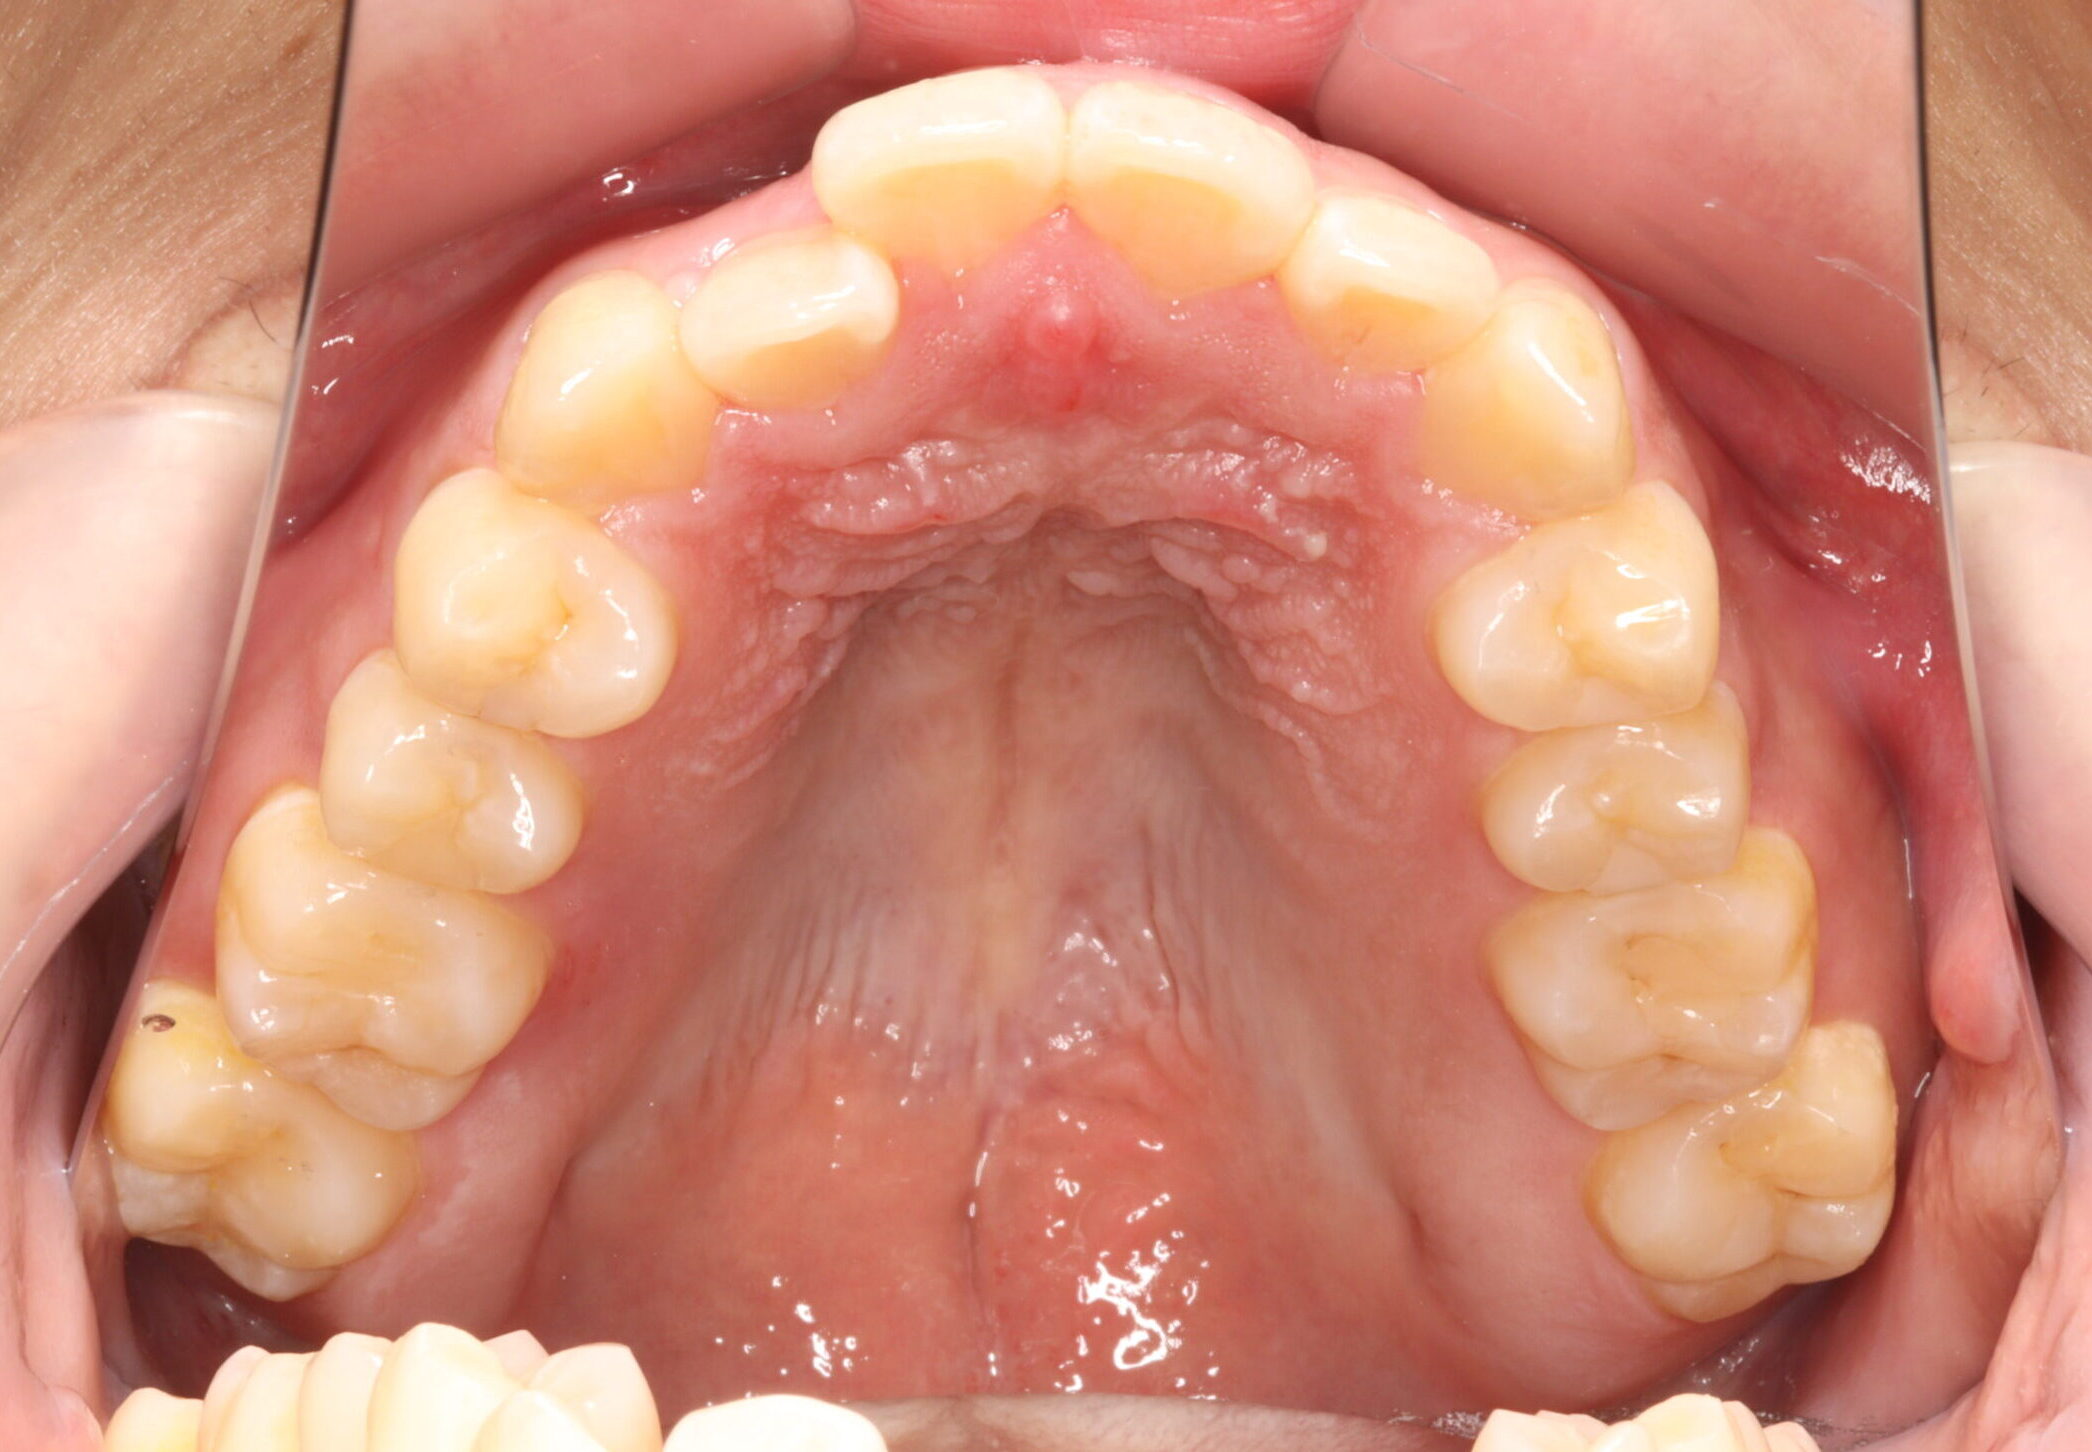

治療前

【診断】開咬、叢生(でこぼこ)、上下顎前歯唇側傾斜、舌突出癖

【治療方法】マルチブラケット装置にて排列を行う。咬合の確立のため顎間ゴムを併用し、舌突出癖の改善のため筋機能療法を行う